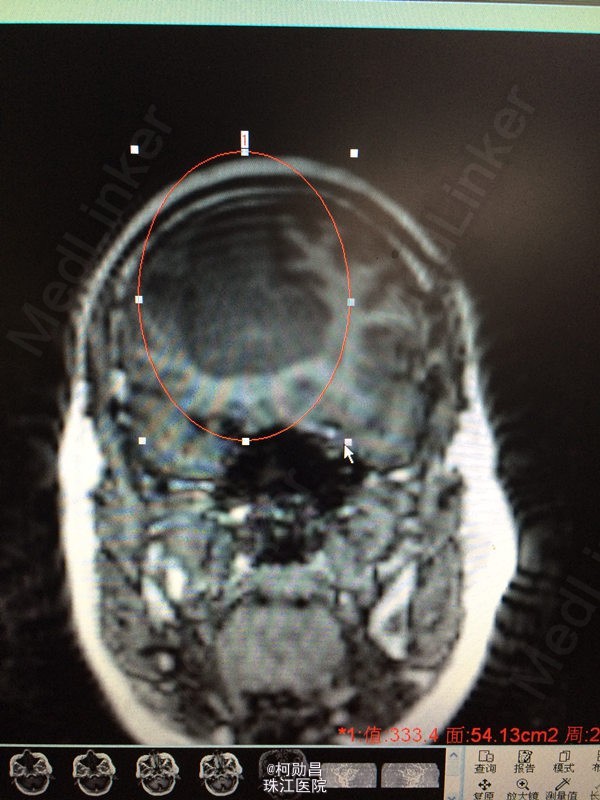

患者 62岁女性,因“发现右侧大脑镰旁肿物2天”入院,症状表现为:反应迟钝,懒言,无其他症状。MR提示“右侧大脑镰旁肿瘤,考虑脑膜瘤”